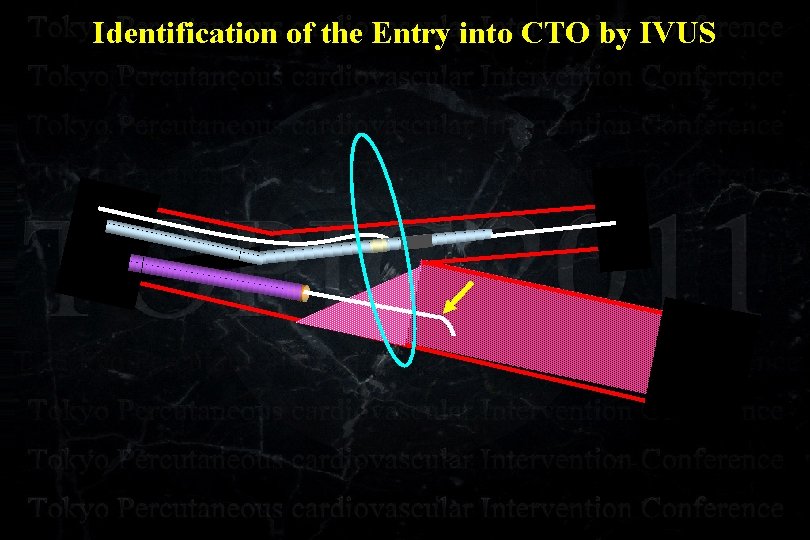

Identification of the Entry into CTO by IVUS